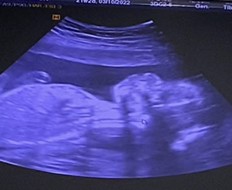

บ้านนี้ชอบโชว์จู๋คะ 23w หนัก700กรัม